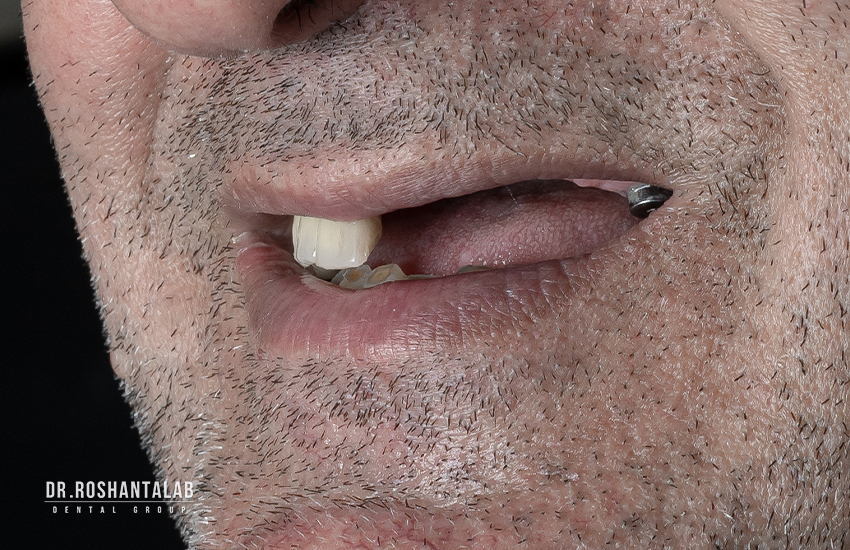

تاثیر روی زیبایی شناسی چهره

دندان های شما روی ساختار و شکل چهره شما تاثیر می گذارند. از دست دادن دندان روی زیبایی شناسی چهره تاثیر بسیار زیادی دارد. استخوان فک تحلیل رفته در اثر از دست رفتن دندان، چهره شما را بسیار پیرتر نشان می دهد. اگر به چهره افرادی با دست دندان متحرک که دندان خود را بیرون آورده اند دقت کنید، متوجه تاثیر نداشتن دندان بر ظاهر فرد می شوید.

دلایل زیادی میتواند موجب شود که شخص در طول دوره زندگی اش دندان یا دندان های خود را از دست بدهد. تروما دندان، ضربه خوردن دندان و حتی کشیدن دندان از جمله این دلایل میتواند باشد. مشکلات در تکلم و تلفظ کلمات، مشکل در جویدن غذا و مشکلات گوارشی، ناهنجاری در اکلوژن دندانها، تحلیل استخوان فک و جابجایی دندان ها بخش کوچکی از مشکلات و عوارض نداشتن دندان است که فرد با آن ها روبرو خواهد شد. به علاوه این موضوع اگر برای دندانهای جلو پیش آید تاثیر زیادی در چهره فرد خواهد داشت. این مورد یکی از مهمترین موارد عوارض بی دندانی است که تاثیر زیادی در اعتماد به نفس فرد دارد. اگر جای خالی دندان افتاده شده جایگزین نشود، بر لبخند فرد هم تاثیر میگذارد و مشکلاتی را هنگام لبخندزدن برای او به همراه دارد.